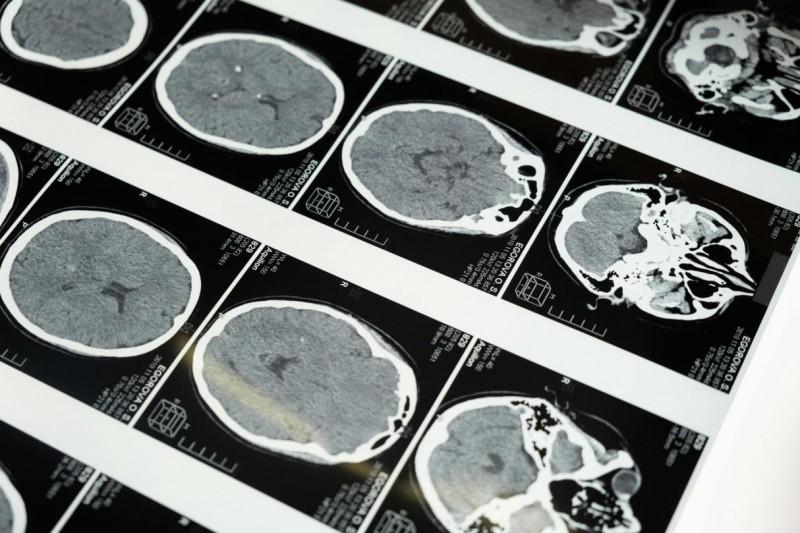

脑梗发作后,是否可以溶栓治疗?记住这几个关键指标

脑梗抢救分秒必争,早判断、早干预,就能多一分希望避免严重伤害。突发脑梗时,能否溶栓核心看三点:发作时间、身体症状、用药禁忌。等待医护时,家属做对急救动作,也能帮患者少受罪。